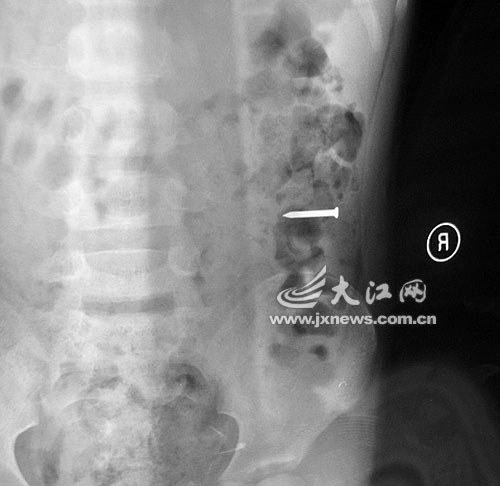

江西留守兒童吞硬幣留父母:勇勇誤吞鐵釘后的X光片

事發當晚,勇勇的奶奶雇了一輛面包車,連夜將勇勇送往都昌縣人民醫院救治。當晚,醫院經過拍片發現,2.5厘米的鐵釘滑到孩子的胃部。